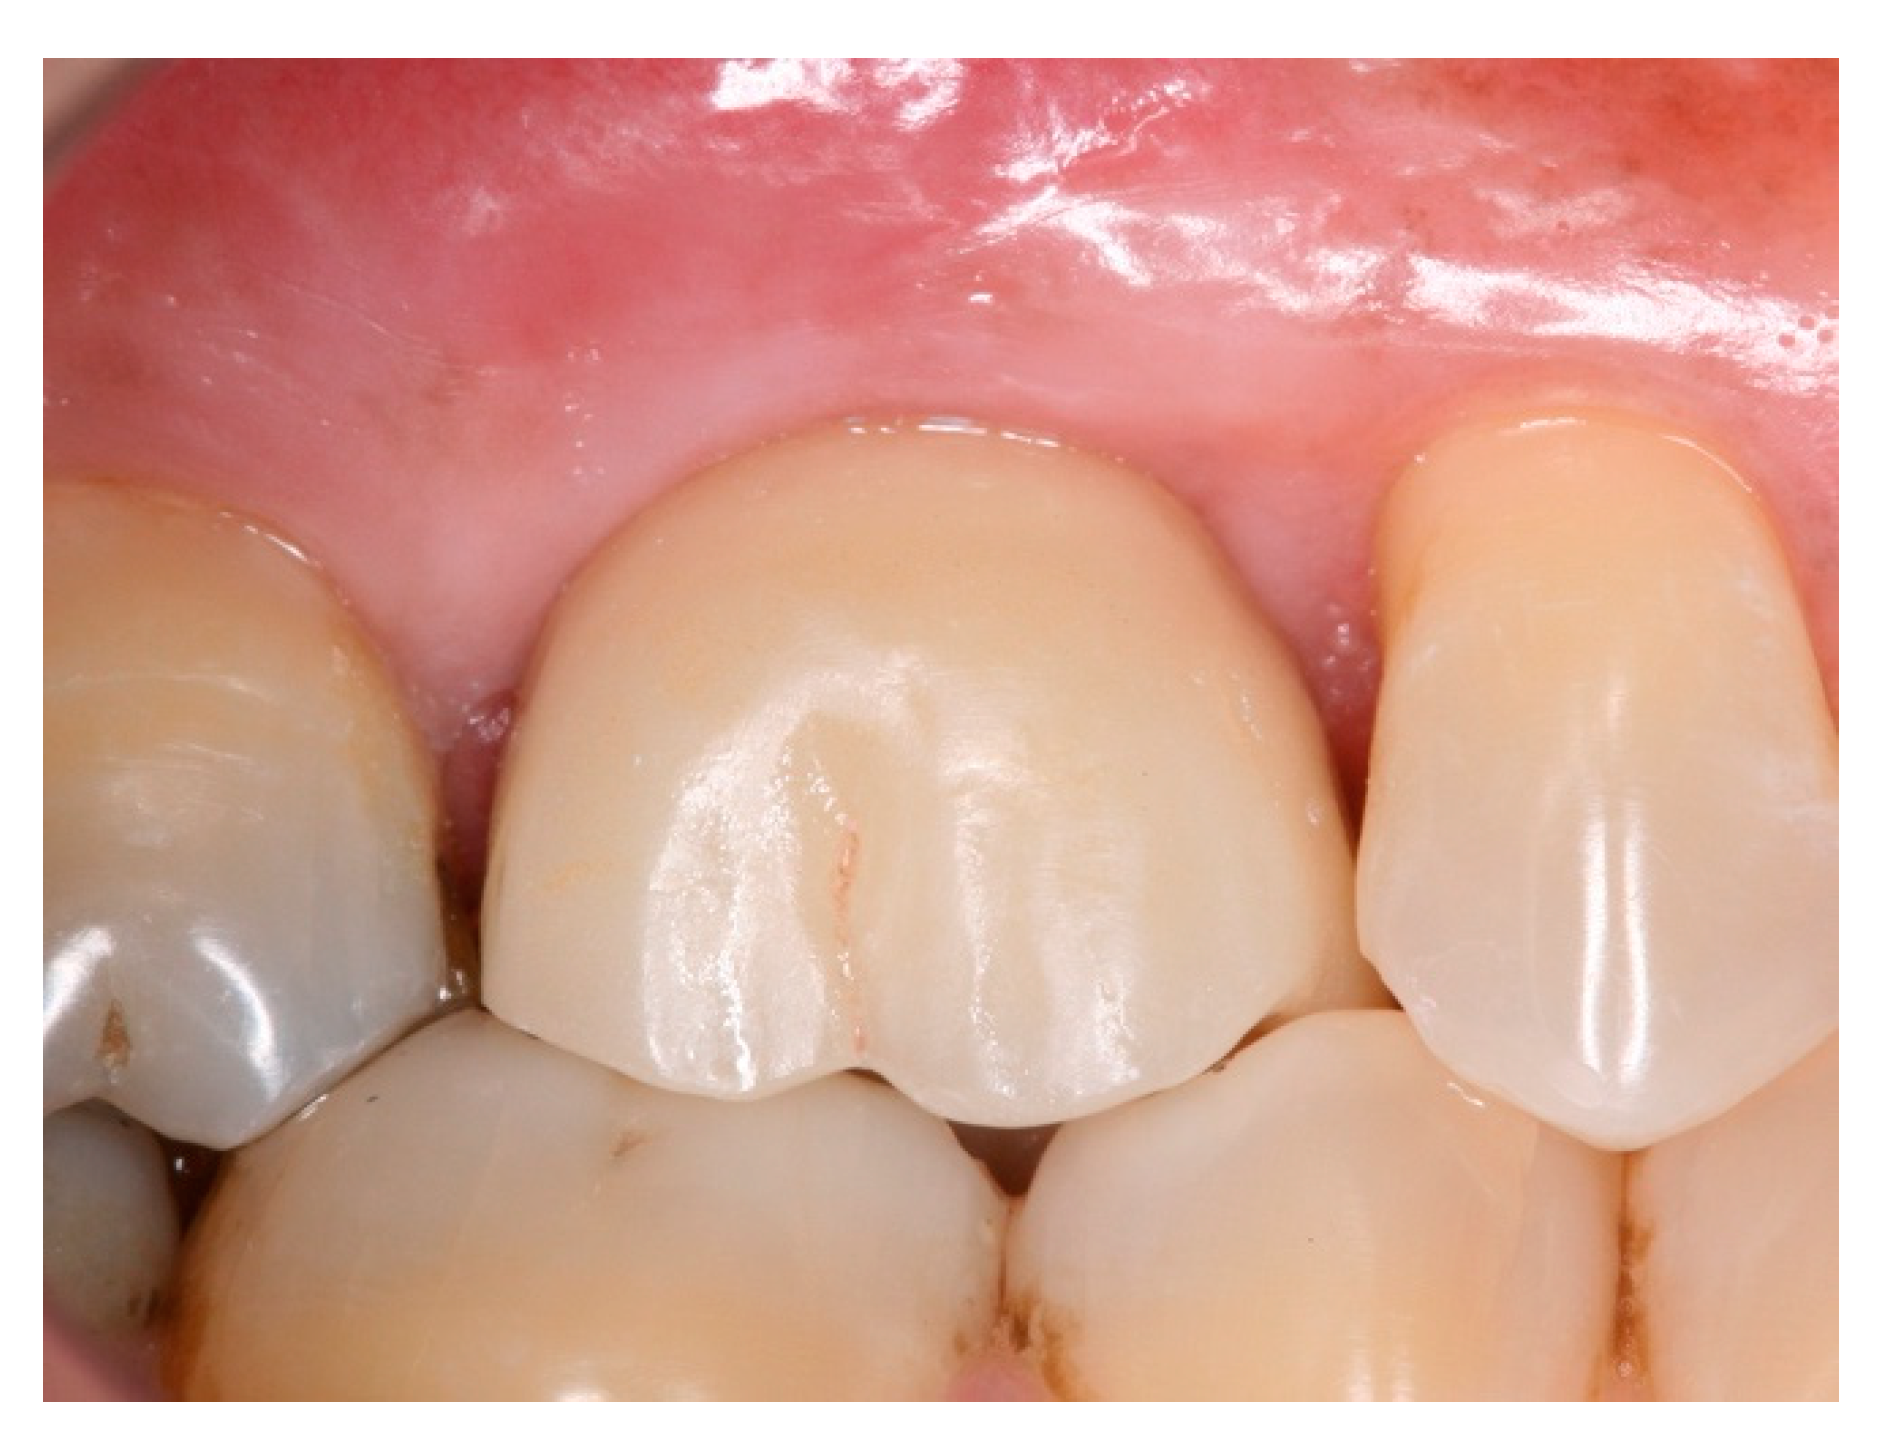

2. Materials and Methods

3. Results